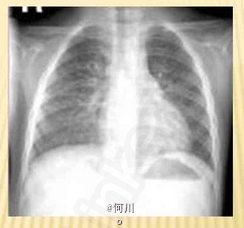

流涕、轻咳、低热、纳差 辅查胸片,X线表现为两肺纹理增粗、增多,模糊。CT可见双肺沿支气管分布的大片状模糊影

患者预后佳